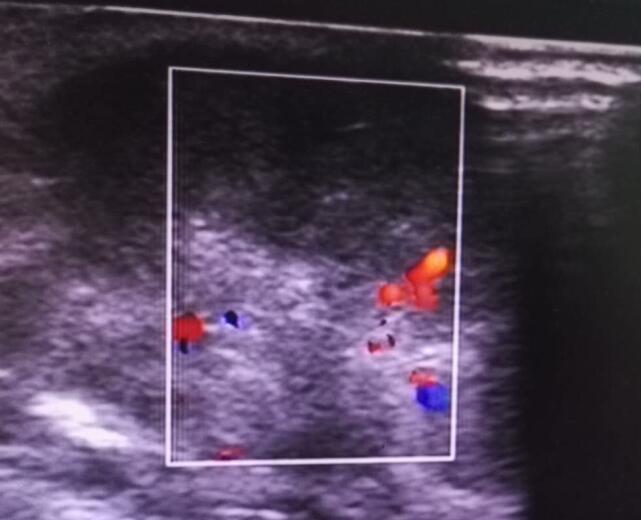

12月底,李某(男)来我院就诊,自述2年前无意中发现右侧乳房肿物,无疼痛,未行诊疗,期间肿物逐渐增大至枣样大小;首诊医师建议行超声检查。超声医师仔细扫查,发现右侧乳头后方可见大小2.7×3.2×2.2cm的实性低回声,形态尚规则,边界尚清晰,CDFI示:其内可见条状血流信号,RI:0.7。扫查患者腋窝,发现数个大小不等的l淋巴结回声,皮髓质分界不清,纵横比>1,皮质增厚,而且回声减低。这些异常特征都倾向于恶性,遂诊断为右乳包块(占位可能性大)。经手术后病理示:右乳腺乳晕下方浸润性导管癌。